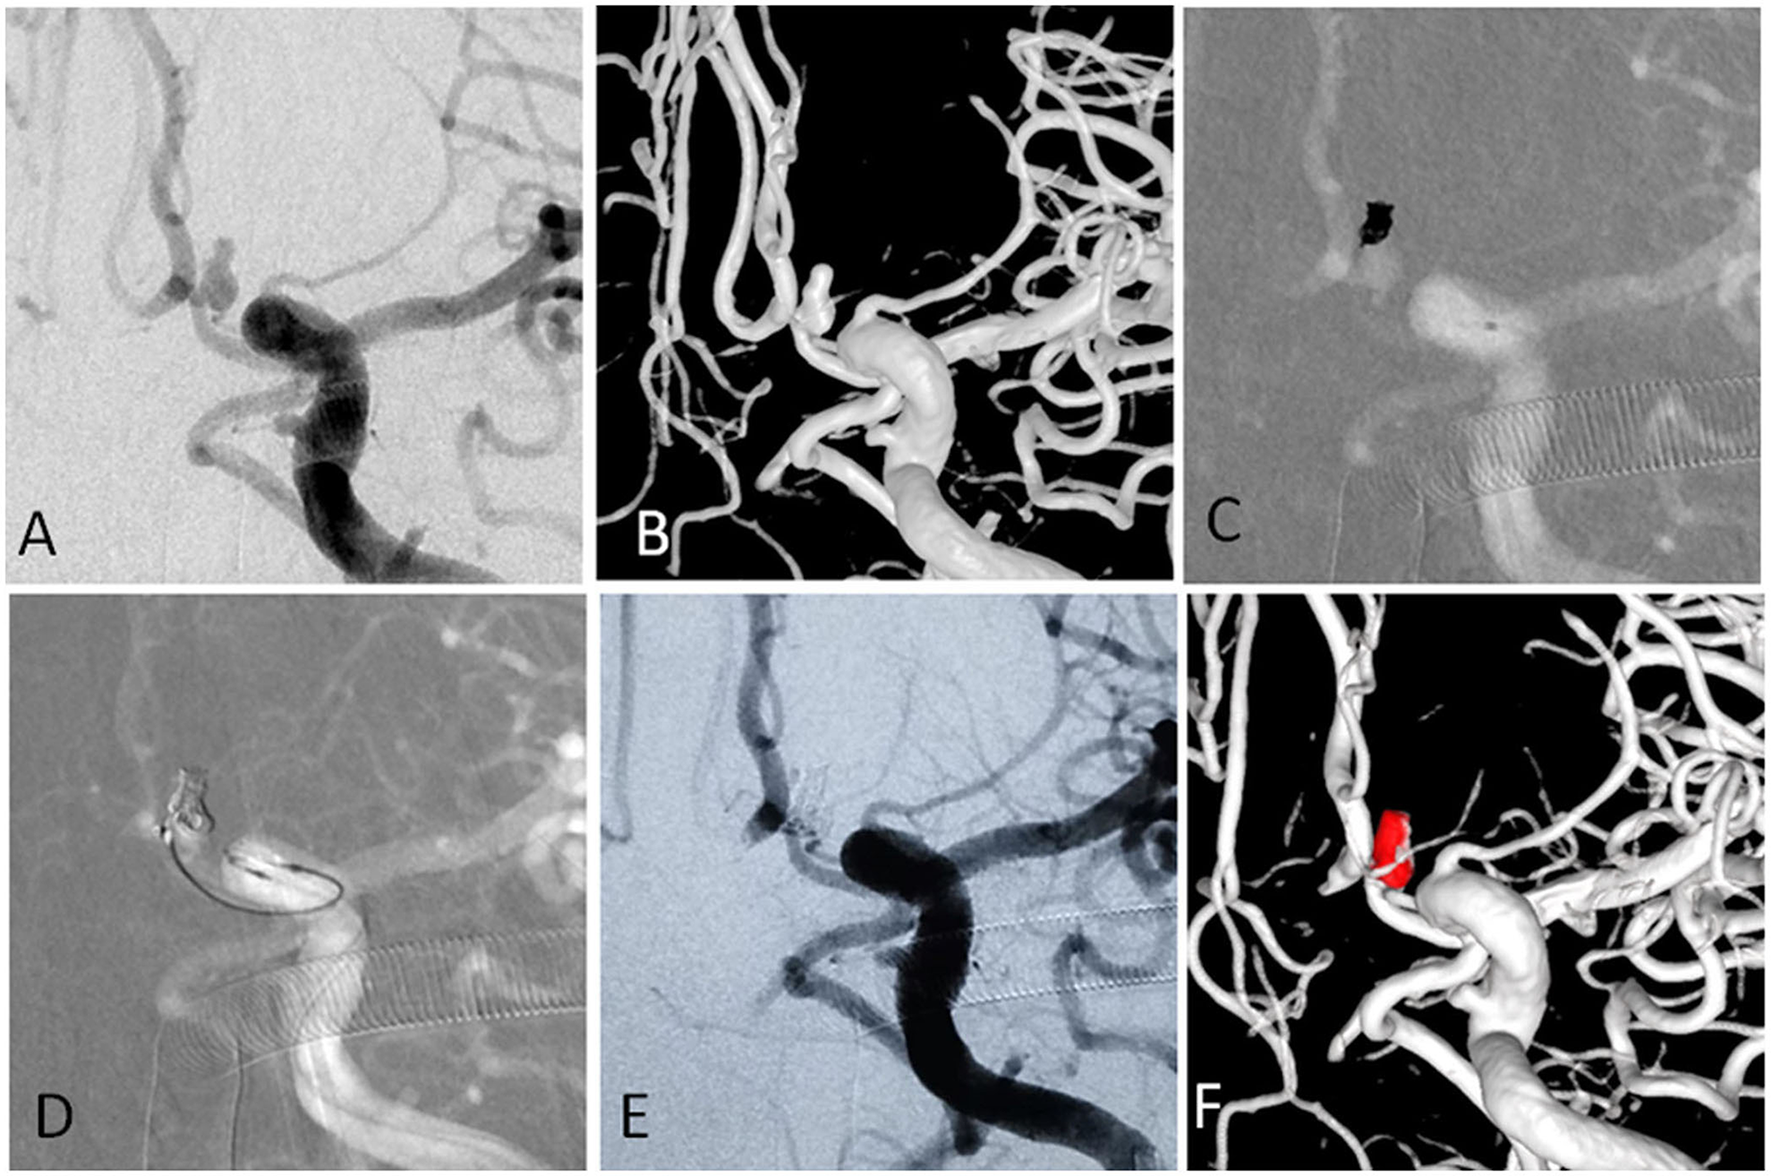

For aneurysms with a large daughter sac (Figure 1), usually one microcatheter is navigated into the daughter sac if there was no difficulty. After the first coil was fully or partially deployed, the second coil was advanced into the aneurysm through the second microcatheter, and the two coils intertwined with each other to form a stable frame. One of the coils was then detached, while the other coil remained attached to the pusher wire. Coils were then introduced through the second catheter until the aneurysm was packed as densely as possible. If blood flow was affected during this procedure, one microcatheter was removed once a stable frame was formed. For wide-necked aneurysms with lateral growth, the double-parallel framing coil technique was first attempted. To this end, two microcatheters with different shapes were consecutively or parallelly advanced into the aneurysm so that the two framing coils form a stable structure. Then, the procedure continued as described earlier. An illustrative case is presented in Figure 2. For branch-incorporated aneurysms (Figure 3), one microcatheter was placed at the orifice of the branch to prevent its occlusion, and a second microcatheter was then used to coil the aneurysm.

Figure 3. (A,B) The angiographic and 3-D imaging showed an anterior communicating artery complex aneurysm. Heubner artery originated from the neck. (C) The first microcatheter was navigated into the aneurysm, and the first coil was fully advanced into the aneurysm. (D) The second microcatheter was navigated into the aneurysm to protect the Heubner artery from being occluded. (E,F) The aneurysm was completely occluded, and the Heubner artery was patent.